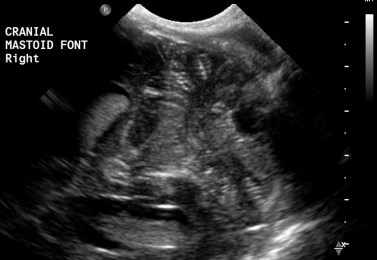

Window to the Posterior Fossa

The mastoid fontanelle provides additional information on the structures of the posterior fossa. It is easily taught and applied, doesn’t extend the length of the examination and has a high diagnostic yield. The mastoid fontanelle is an intregal part of our routine cranial ultrasound series.

The mastoid fontanelle is located above the mastoid tip, behind the ear. The fontanelle is created by the parietal, occipital and temporal bones and is generally closed by 6 mths of post term . Scanning is performed in 2 planes, axial and coronal. The axial plane is a plane through the superior orbital margin to the external auditory meatus. The coronal plane is a true coronal plane through the mastoid fontanelle.